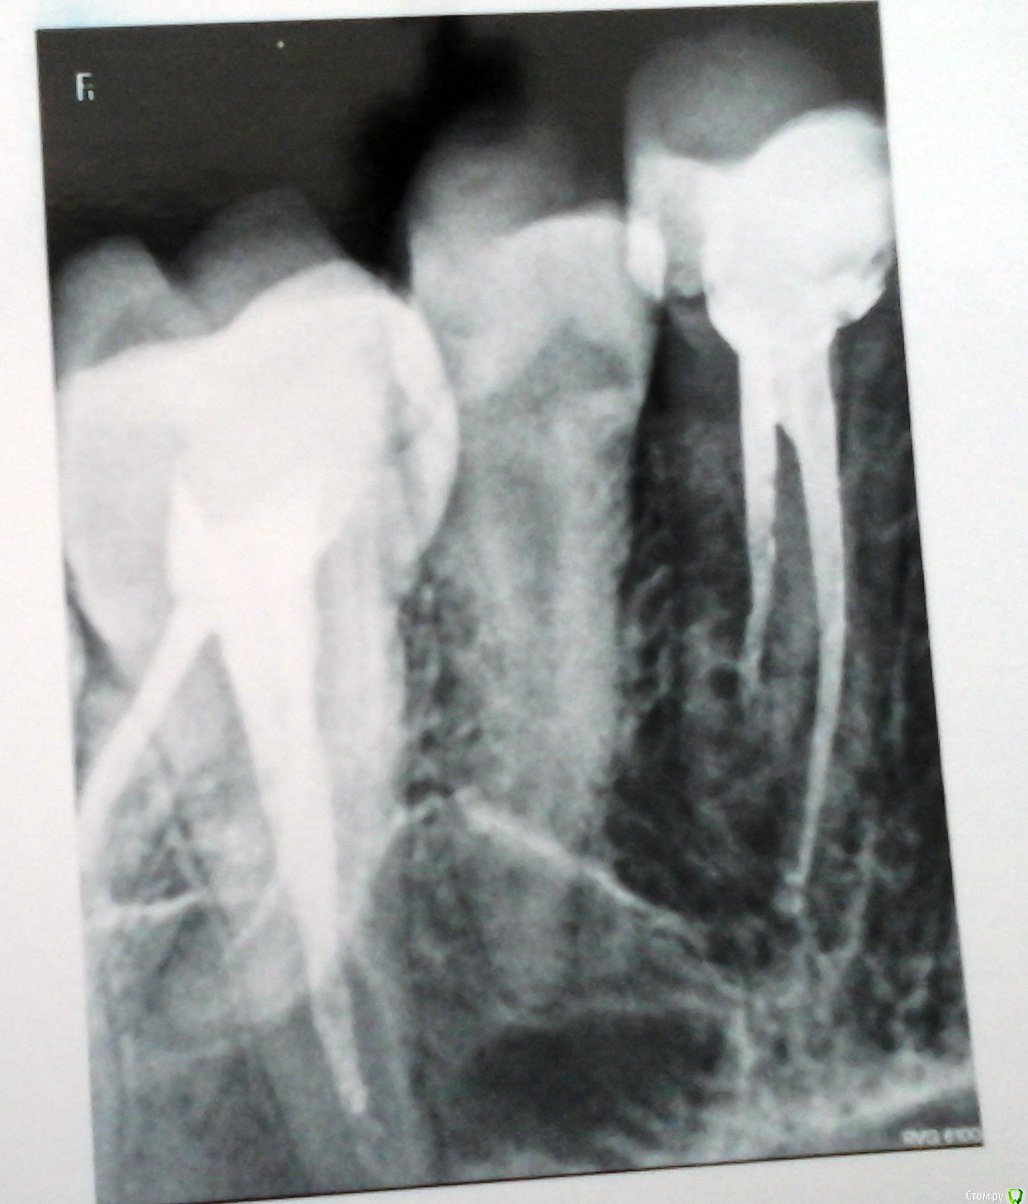

remenikomer Опубликовано 23 февраля, 2017 Поделиться Опубликовано 23 февраля, 2017 Подскажите, на что можно рассчитывать в такой ситуации?Проблема у жены, не у меня.Зуб после лечения, примерно года 3 назад. Сейчас немного припухла щека, боль при открывании рта. Жевать не больно. Решили сделать рентген. Клиники не работают в праздники. Врач, где делали снимок, сказал, что, много гноя и, возможно, долго не вытерпите (все праздники). Зуб, говорит, вряд ли спасти можно. А лечить она в этой клинике не хочет. Хочет в той же, где уже лечила.Подскажите, пожалуйста, что имеем, что ждать? Можно ли спасти зуб? И какая причина этому могла послужить, могло ли это случиться из-за плохого предыдущего лечения? Ссылка на комментарий

DmitrySH Опубликовано 23 февраля, 2017 Поделиться Опубликовано 23 февраля, 2017 Очаг воспаления вокруг одного из корней 4-го зуба. Но снимок лучше переделать, качество оставляет желать лучшего. 2 Ссылка на комментарий